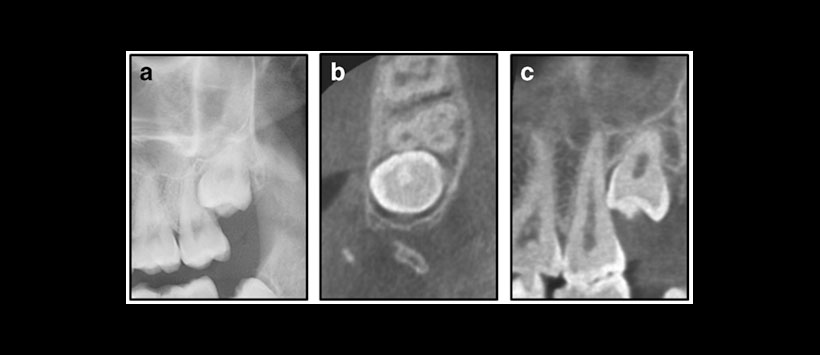

Para lo cual 111 terceros molares impactados, examinados clínicamente (incluyendo una panorámica), en 86 pacientes (edad media 26 años, rango 15-55) fueron remitidos para CBCT bajo sospecha de patología / reabsorción radicular en el segundo molar, según la información de la imagen panorámica. (Figura 1 y Figura 2)

Los hallazgos en CBCT a menudo cambiaron el plan de tratamiento. La reabsorción radicular externa observada en CBCT fue el principal factor decisivo para eliminar el segundo en lugar de la tercera molar.